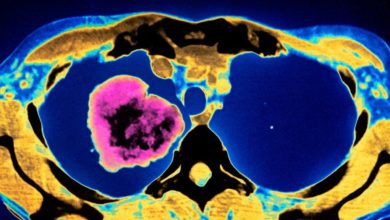

Health USAFewer Cigarettes, Better Treatment: Lung Cancer now Less Deadly in the US

A new study, led by the National Cancer Institute (NCI) and published in the New England Journal of Medicine, shows that recent advances in non-small cell lung cancer (NSCLC) treatment have contributed to a sharp mortality drop in the United States in the recent years.